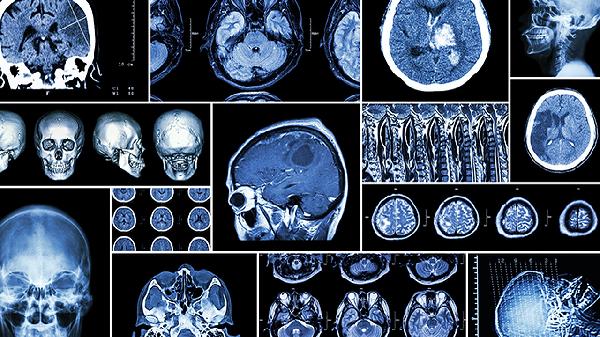

术后需定期进行CT或MRI检查,评估修复效果及植入物稳定性。首次复查通常在术后1个月,之后根据医生建议安排后续检查。通过影像学检查可及时发现脑水肿、植入物移位等问题,避免并发症加重。